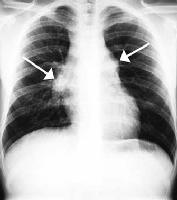

The commonest causes in India for this gland enlargement ( as seen by the arrows in the xray on the right ), are tuberculosis, sarcoidosis, cancer of the lymph glands or a non-specific infection. As the treatment for these conditions are different, it is important for the treating physician to have a microscopically proven diagnosis.